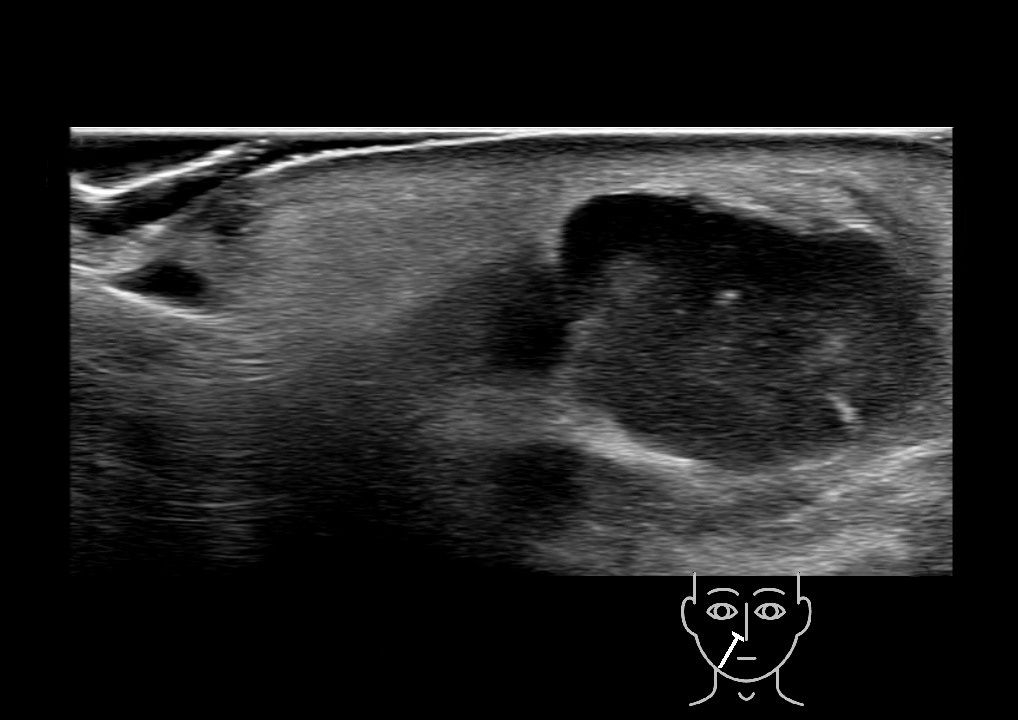

With ultrasound signs of inflammation can be visualized. Edema can be seen as a hyperechoic appearance of the subcutaneous fat, sometimes separated by hypoechoic fluid filled area’s, known as cobblestone appearance. Increased vascularization (hypervascularity) can be seen on colour Doppler. An abscess will appear as a fluid collection appearing as an irregular hypoechoic area with heterogeneous internal echoes and a thickened wall. Posterior acoustic enhancement can be present, and there is vascularity around but not within the mass. Under ultrasound guidance, abscesses can be managed by needle aspirations (18G) under antibiotic cover.

Study the first image to recognize the different layers. If you are sure about the layers, swipe to the second image to view the answer (if applicable).